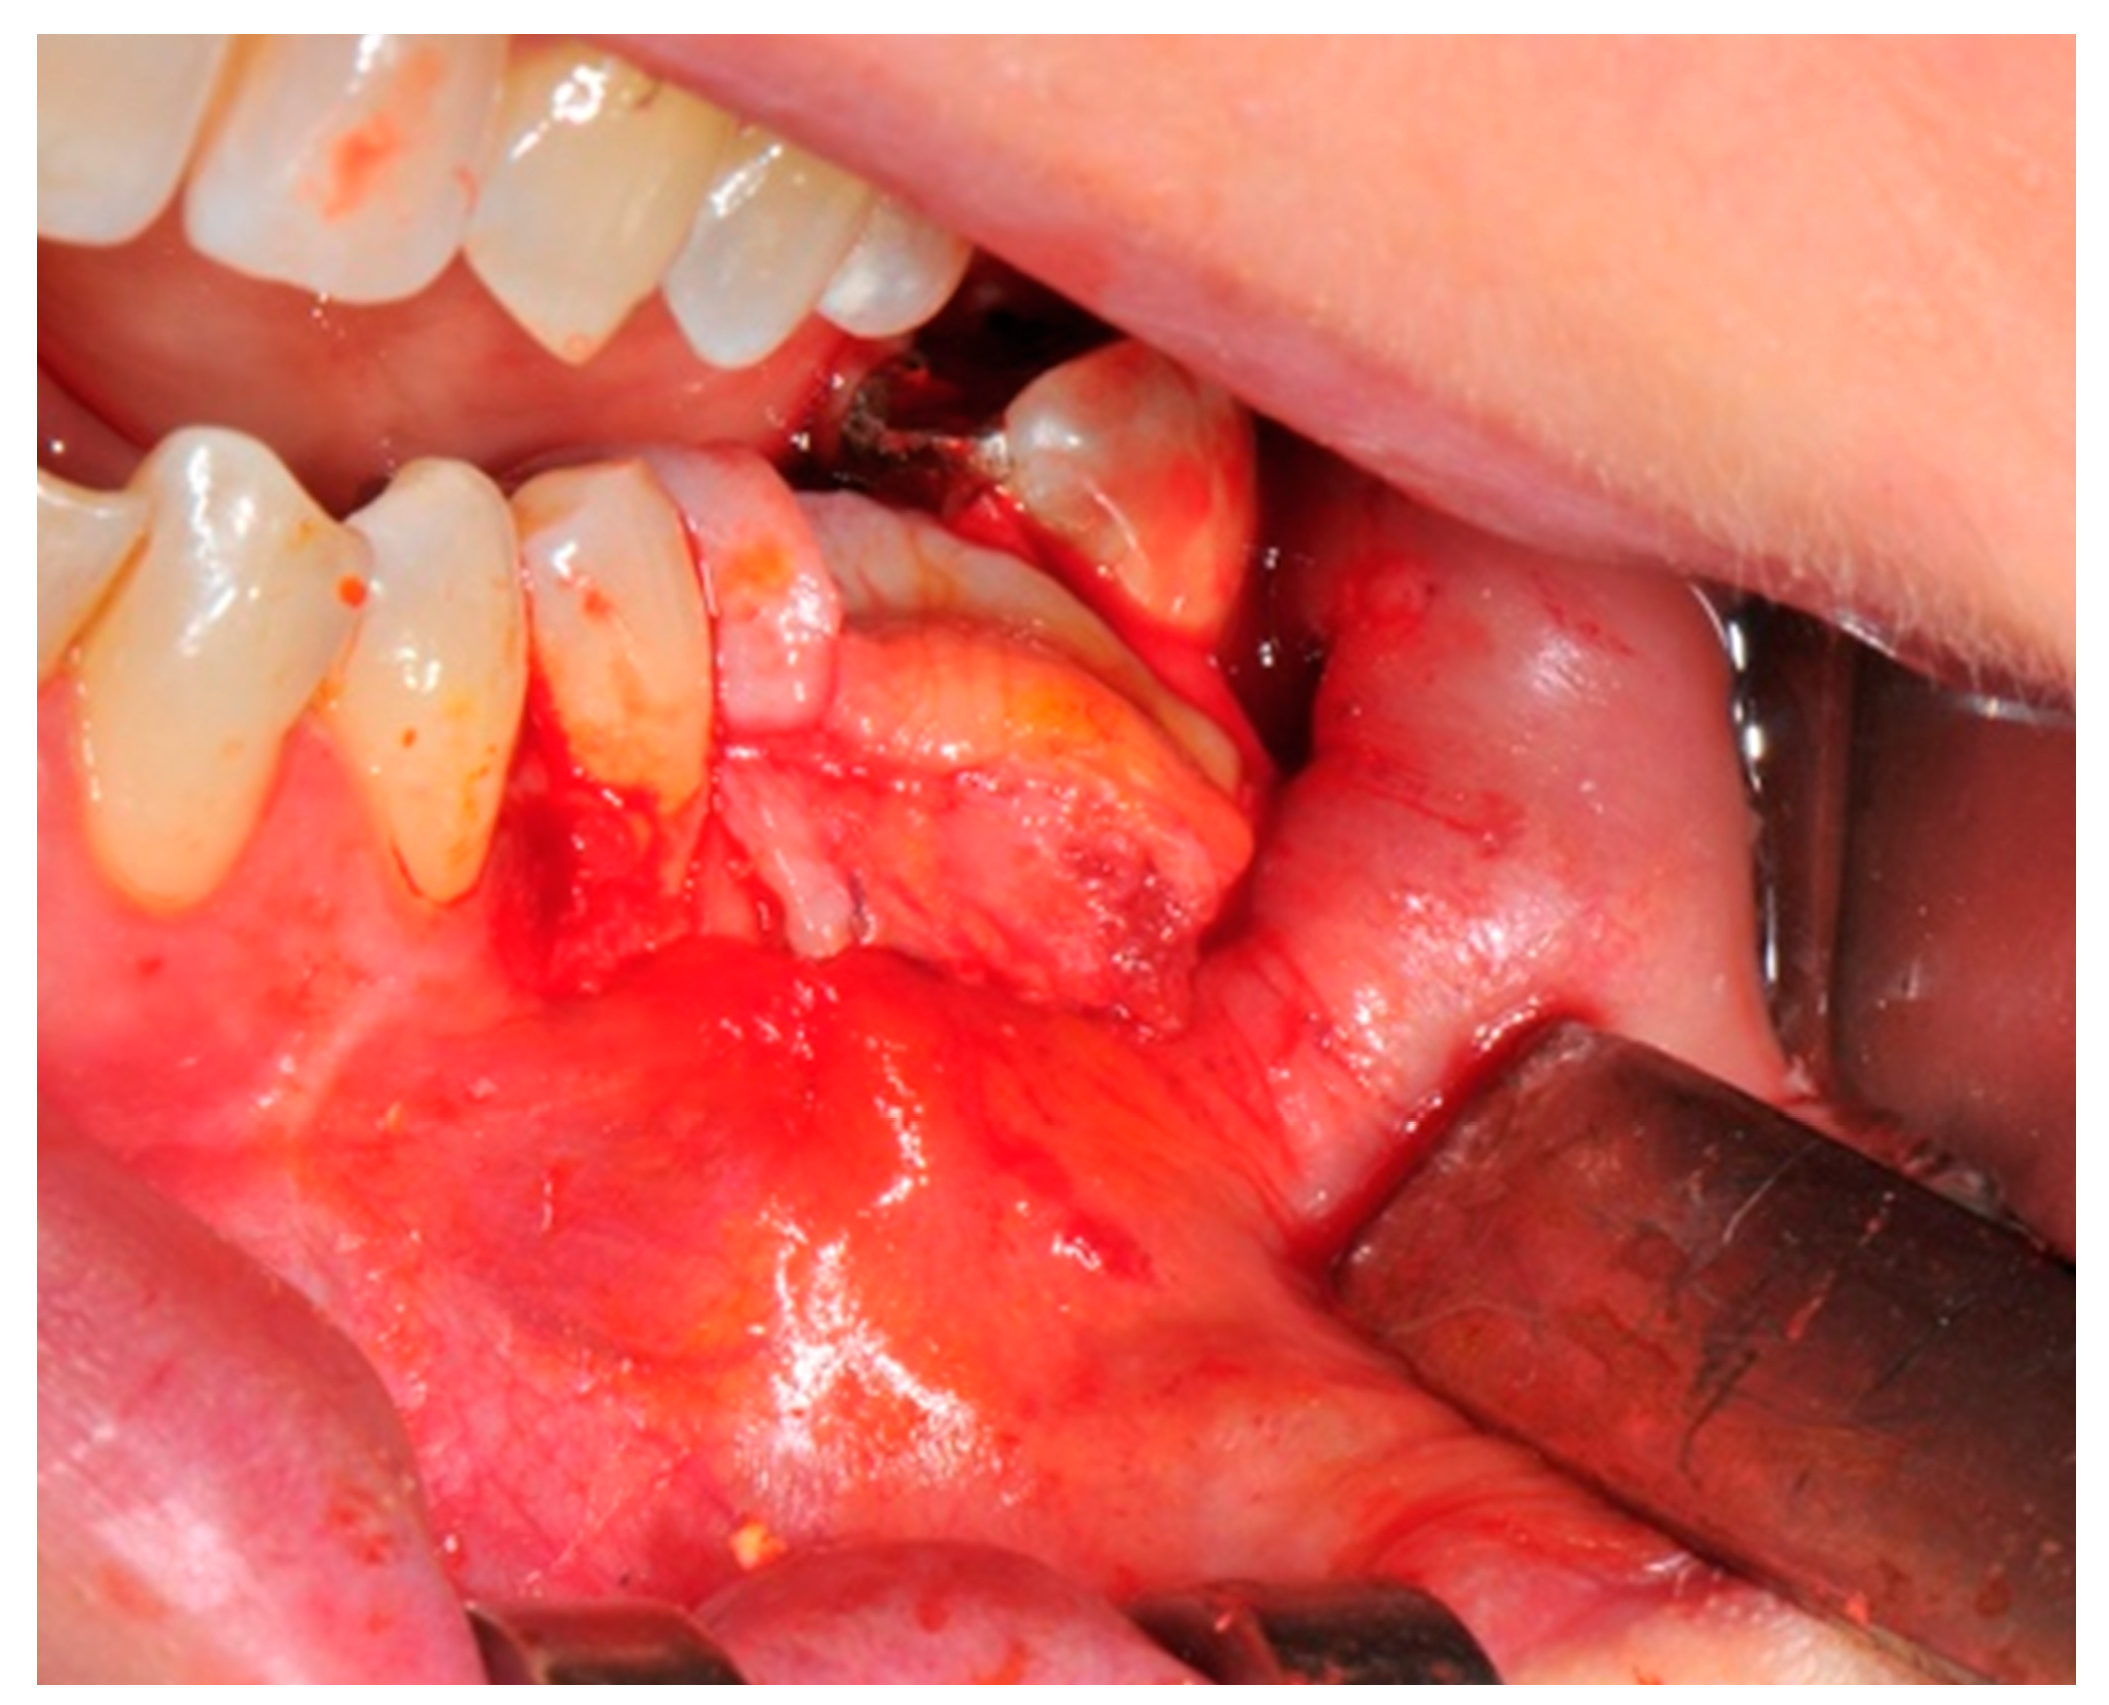

- Passivation of the flap: Delicate periosteal incisions are performed to achieve mobility of the flap and allowing first intention closure, creating a passive/tension-free flap in order to avoid detrimental tension or graft exposure (Figure 11).